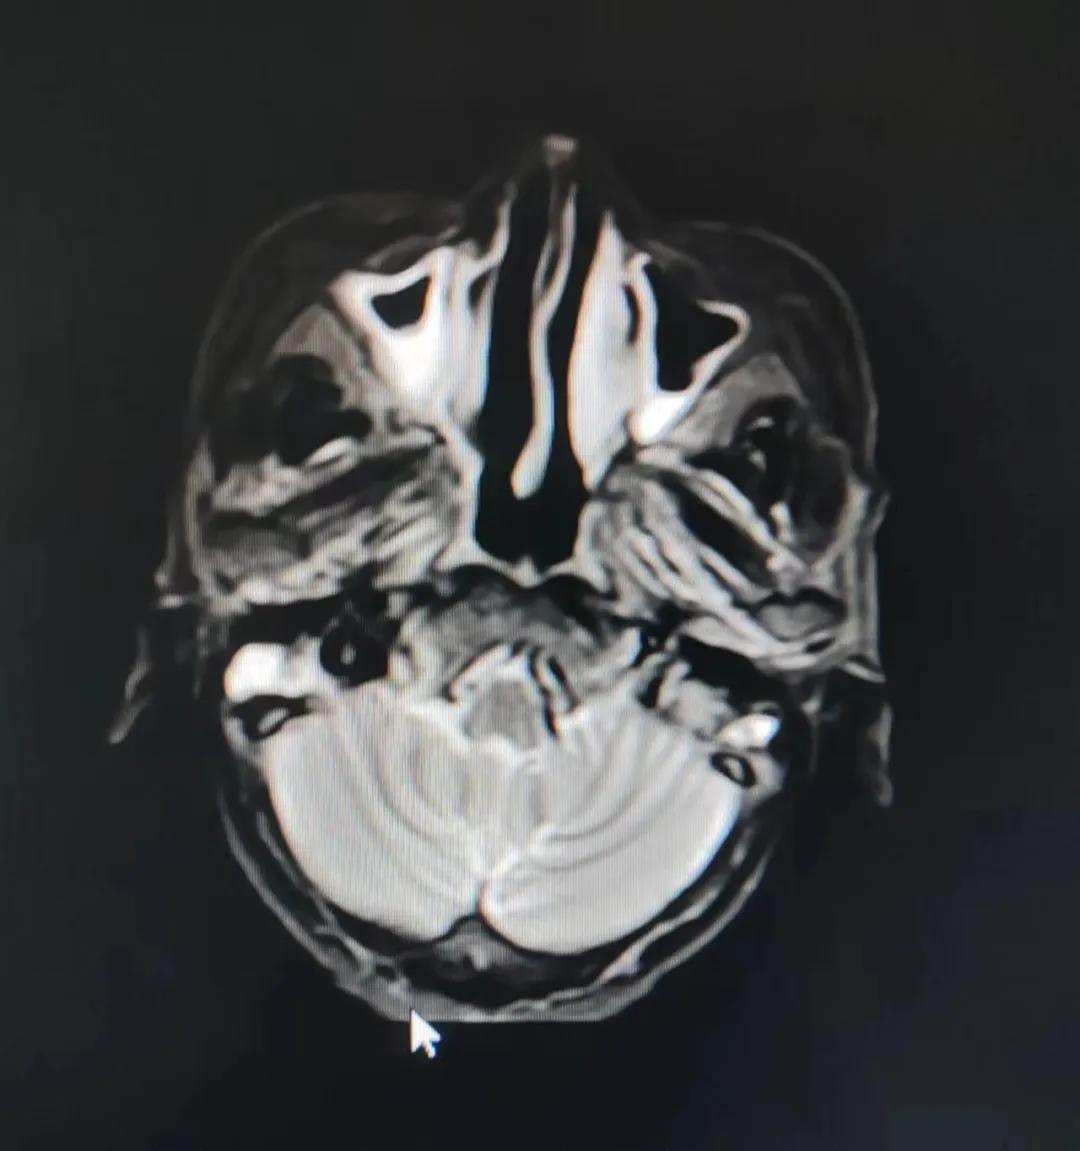

治療前

老人因鼻部腫物堵塞鼻腔并且侵犯鼻咽導致鼻塞、疼痛、吞咽困難,身心都備受煎熬,趙亮主任在詢問其病史期間幾度落淚。趙亮主任向患者及家屬解釋說:“現(xiàn)代放療比過去的傳統(tǒng)放療設備先進,技術不斷提升,能對腫瘤區(qū)域的照射劑量進行優(yōu)化,做到準確定位、精準照射,同時,最大限度地降低正常組織的受量,對全身情況影響很小。”

考慮到患者年齡較大、體質(zhì)差,手術難度大,且常規(guī)的放射治療難以保護患者晶體造成患者雙眼視力損傷,放療團隊以最快的速度制定了精準放射治療方案并開始為其實施治療。僅僅數(shù)日后,老人腫塊出血即得到控制,腫塊明顯縮小,放療20次后腫塊迅速縮??!